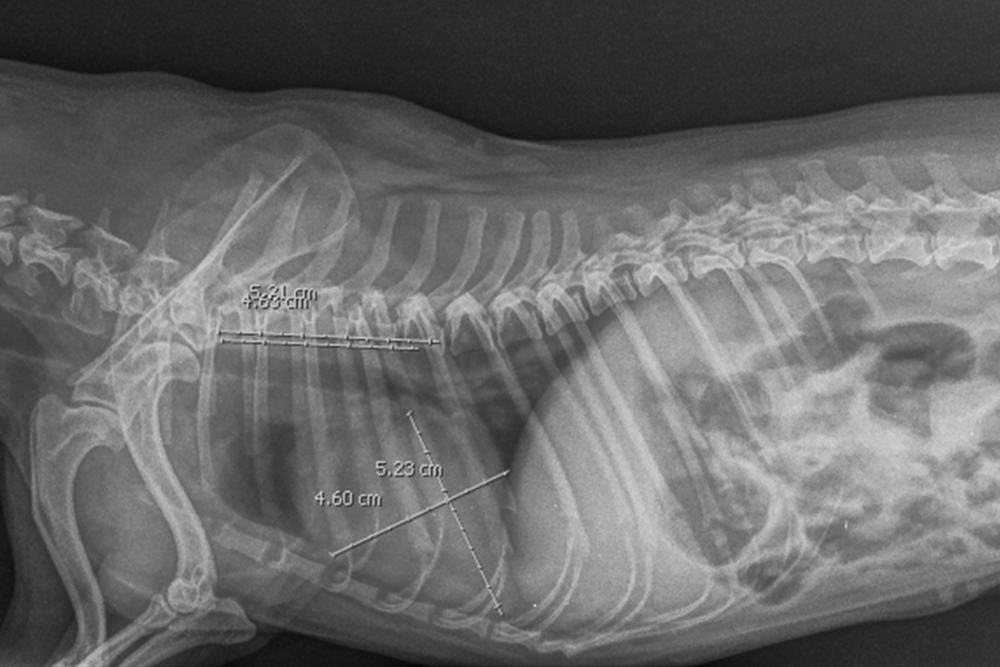

- La radiographie thoracique a pour but de voir la taille du cœur (un cœur trop gros peut indiquer une insuffisance cardiaque) et de repérer une accumulation de liquide dans les poumons.